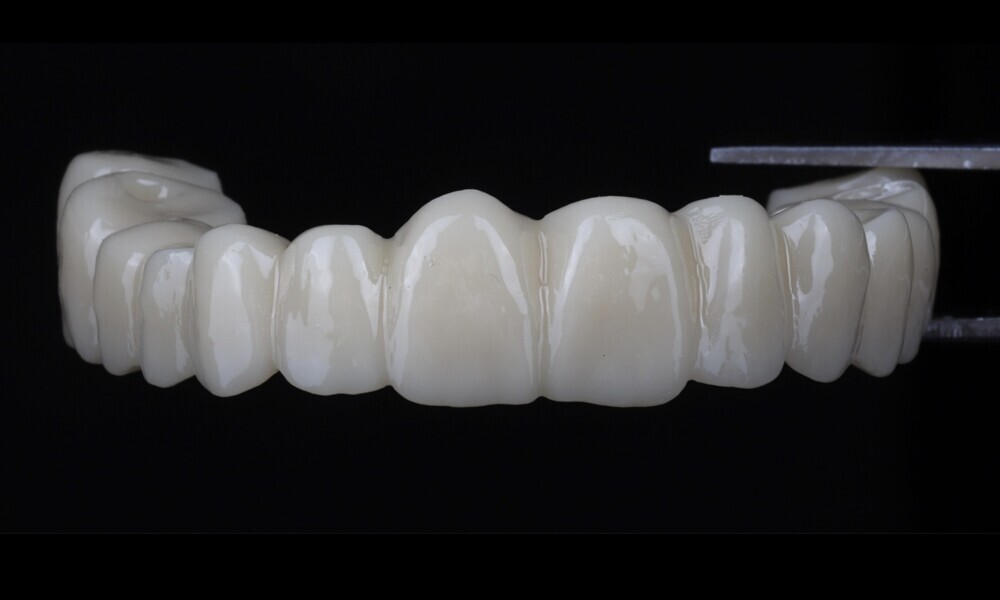

During the next visit, the milled prototype and verification jig were tried in, and the design and manufacturing of the final prosthesis were completed (Figs. 47 & 48). The final abutment utilised was Variobase for bridge (Straumann), placed on top of the screw-retained abutments. The material chosen for the final prosthesis was monolithic zirconia (Figs. 49 & 50).

The delivery of the final prosthesis was then performed, and the aesthetics, occlusion and function were verified (Figs. 51–55). The panoramic control radiograph showed that all measurements were within expected ranges (Fig. 56).

At the 18-month follow-up after completing the treatment, an intra-oral, extra-oral and radiographic evaluation were performed. No pathologies were observed, and the results remained stable over time (Figs. 57–62). The patient expressed his satisfaction with the treatment outcomes, stating, “Seeing my new smile before starting the procedure was a game-changer. I was confident from the beginning that my final result would be as I had imagined.”